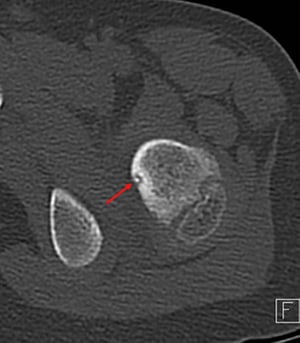

左股関節痛のある6歳の小児における大腿骨近位部(隣接する骨は骨盤枝)のCT水平断像で,中心石灰化を伴う典型的な透明のnidus(矢印)が認められる。このCT画像では古典的な標的様病変が認められる。